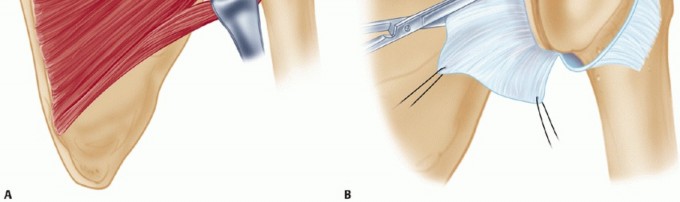

A longitudinal incision in the posterior axillary fold is made beginning at a point 2 cm medial to the posterolateral corner of the acromion and extending distally, following the posterior axillary line (TECH FIG 3).

- TECH FIG 3 • The posterior longitudinal incision begins about 2 cm medial to the posterolateral corner of the acromion and extends into the axillary crease.

- TECH FIG 4 • With the deltoid fibers bluntly split, a vertical incision is made directly through the infraspinatus while keeping a small stump of infraspinatus tendon attached laterally for reattachment later.

Third, the infraspinatus may be completely detached, leaving a 2-cm remnant of the tendon still attached for later repair (TECH FIG 4). It is tagged and carefully released from the underlying thin capsule. - Capsulotomy

A vertical capsulotomy is made on the humeral side with the arm in neutral rotation (TECH FIG 5A).

TECH FIG 5 • A. The infraspinatus is elevated as a single layer, exposing the underlying posterior capsule. A vertical capsulotomy is then made based on the humeral side from the 12 o'clock to the 6 o'clock position. B. Traction stitches are then placed as the medial capsule is divided horizontally, between the sutures, toward but not through the glenoid labrum.